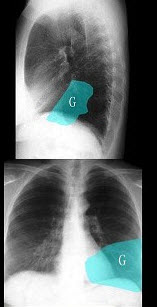

22、单项选择题

患者,女,46岁,胸闷气短1月,伴全身乏力,咳嗽,发热。胸片示:中上纵隔增宽,右缘呈波浪状改变。白细胞:8.5×10/L。

最可能的诊断是()

男,74岁,咳嗽,咳痰1月余,咯血丝痰1周伴胸痛,胸片如图,最可能的诊断为()